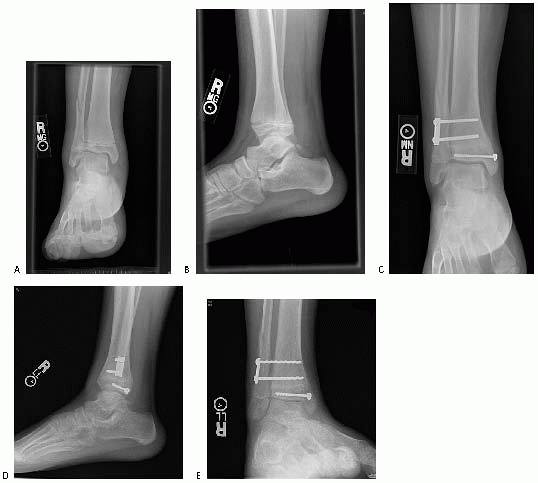

![]() |

FIGURE 26-16 Triplane with deltoid injury and syndesmosis widening with stress views. A,B. Injury films. C-E. Postoperative films.

mortise view of the ankle is essential in addition to anteroposterior

and lateral views. On a standard anteroposterior view, the

lateral

portion of the distal tibial physis is usually partially obscured by

the distal fibula. The vertical component of a triplane or Tillaux

fracture can be hidden behind the overlying fibular cortical shadow.107 A study by Vangsness and coworkers186